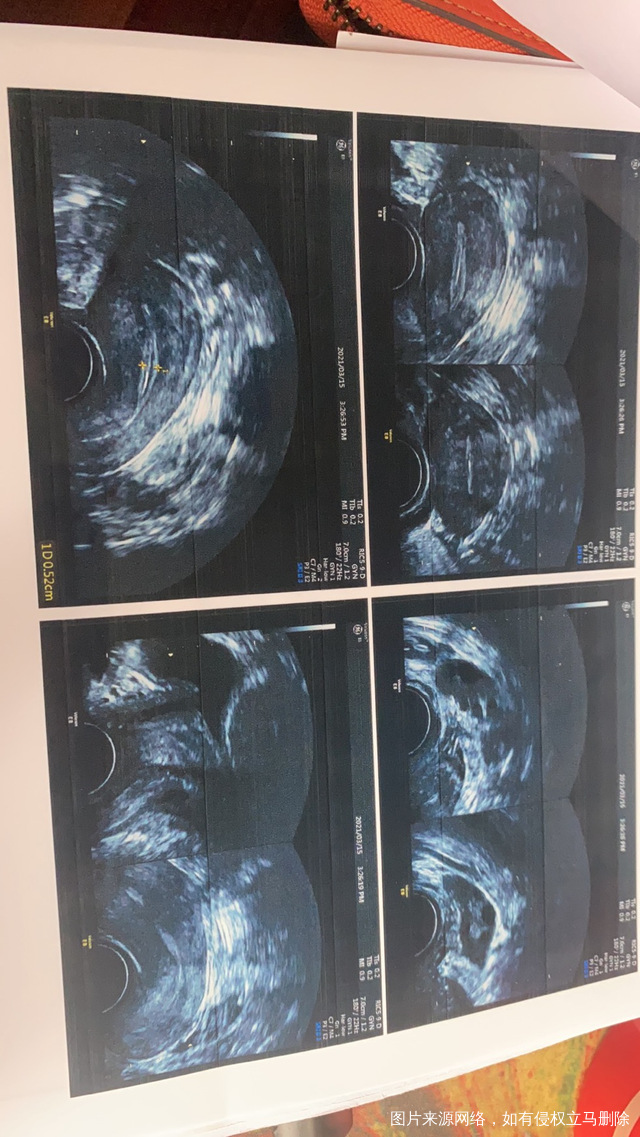

医生您好麻烦您帮我看一下我做的三维彩超报告是